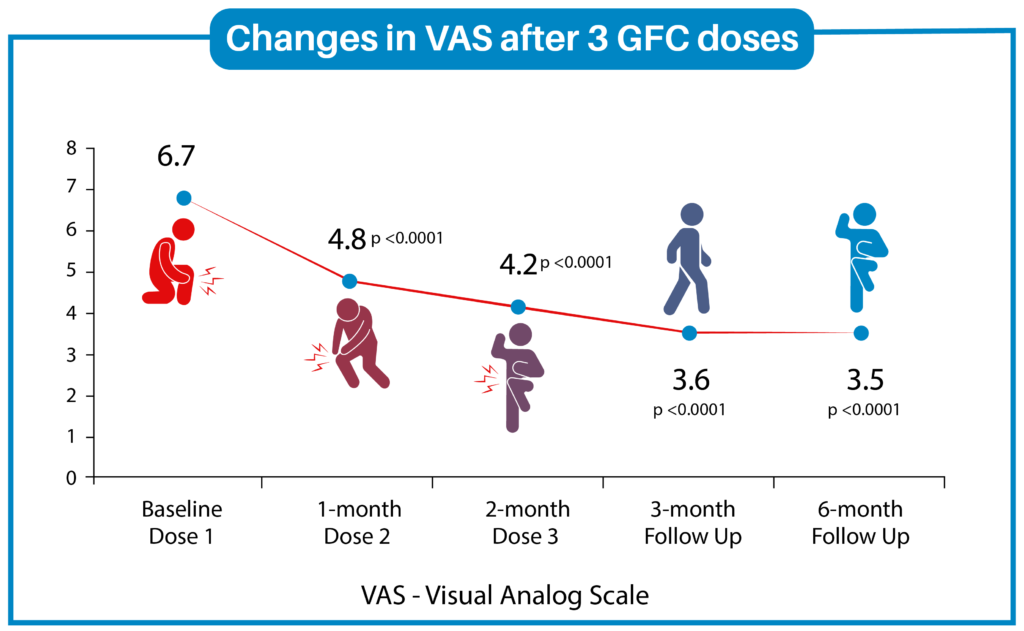

Results